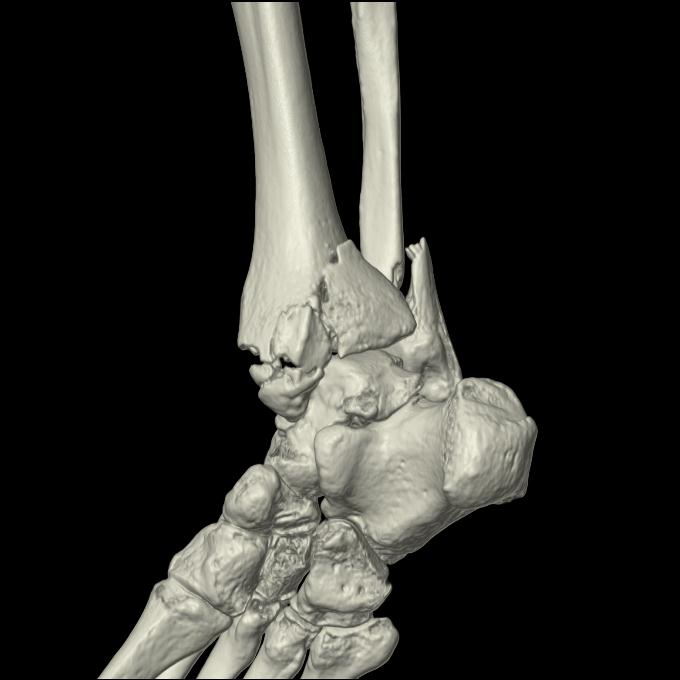

56476 8/28 4R 1/21 2R 左足関節 デジカメ写真 72歳女性 右足関節AS

102755 1/4 2R 1/15 2R 右足関節 68歳女性 右三果脱臼骨折